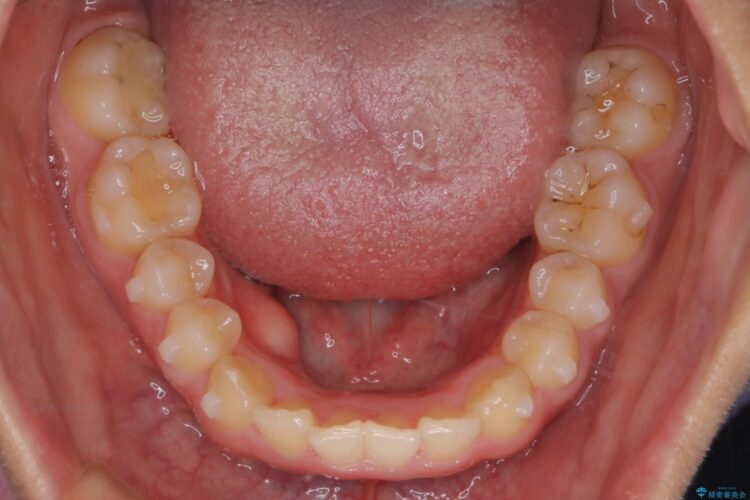

下の前歯のガタつきと正中のズレが気になるとご来院された患者様です。

軽度のガタつきだあったのと、かみ合わせがやや深かったため、インビザラインで治療を行うこととしました。

IPR(歯と歯の間を削る処置)と歯列拡大をすることでガタつきをとります。

前歯のガタつきを改善するのに時間がかかりましたが、ガタつきもかみ合わせも綺麗になりました。